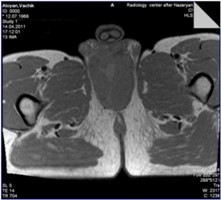

ՈւՁՀ – որովայնի և կոնքի օրգաններն անփոփոխ են, հետորովայնամզային մեծացած ավշահանգույցներ չկան: Շեքի շրջանում առկա է մոտ 12,0 x 7,0սմ չափերի, անհարթ մակերեսով, համեմատաբար հստակ եզրագծերով ուռուցքային գոյացություն: Կոմպյուտերային տոմոգրաֆիա ն/ե կոնտրաստավորմամբ և ՄՌՏ – նշված 12,0 x 7,0սմ չափերի հյուսվածքային գոյացություննարտաօրգանային է, չի բացառվում հպում առնանդամի աջ ոտիկին և միզուկի սպունգանման հատվածի հետ (նկ. 2):

| Նկար 2 | |